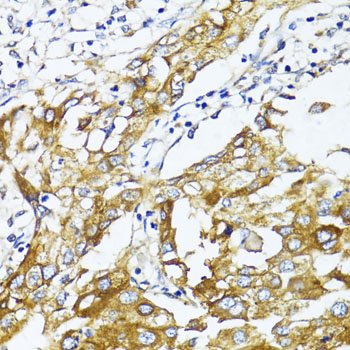

Immunohistochemistry of paraffin-embedded human liver cancer using GLUT4 at dilution of 1:100 (40x lens).